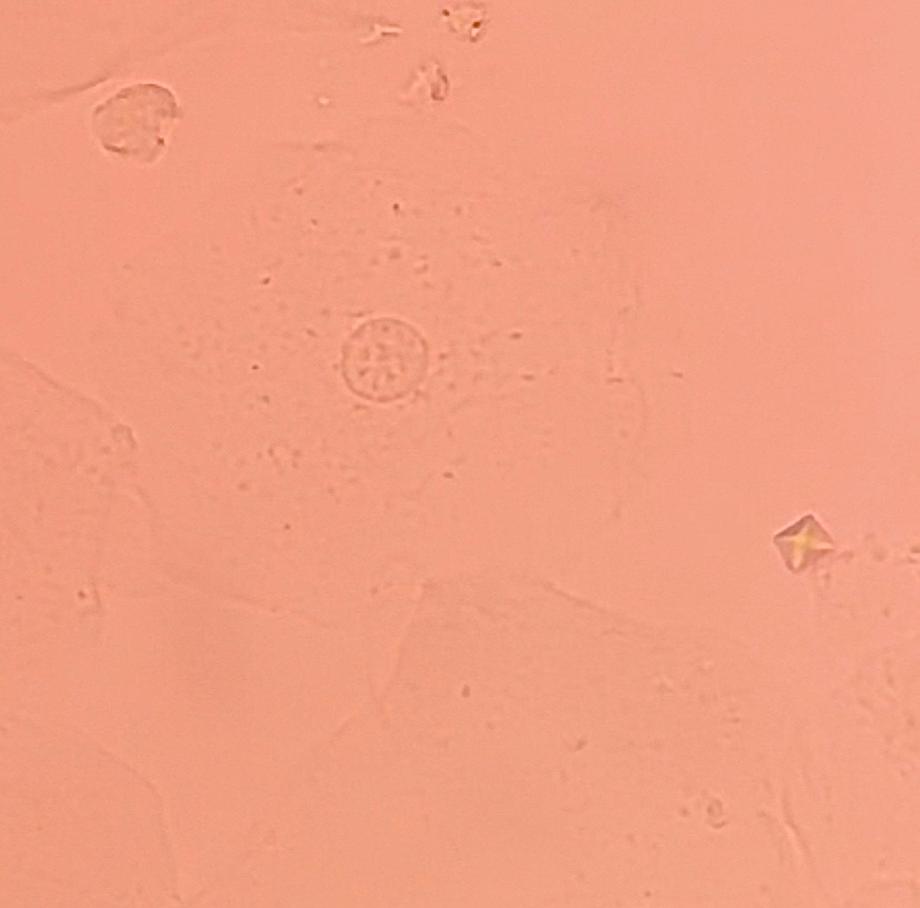

본문 시작 요 pH 측정 임상병리학과 403 2025-05-19 요 pH를 측정해본 후 산성뇨, 염기성뇨와 관련된 질병에 대해 알아보는 시간을 가졌습니다 목록 이전요시험지 테스트 다음 환자 검체를 이용한 요침사 검경 & 회식 만족도조사 만족도 조사 이 페이지에서 제공하는 정보에 대하여 만족하시나요? 매우만족 만족 보통 불만족 매우불만족